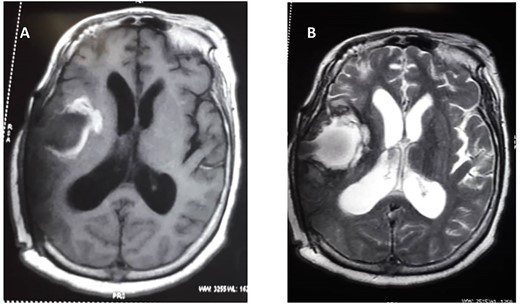

Cranial magnetic resonance image (MRI) revealed a large heterogeneous solid mass with multiple cystic areas in the right parietal lobe; this was associated with marked mass effect (Fig. 1A and B). The total brain lesion measured 7.2 × 6.0 × 7.3 cm, with the solid lateral component measuring 2.9 × 2.8 × 4.1 cm. There was heterogeneous contrast enhancement with extensive perilesional oedema. Magnetic resonance spectroscopy revealed decrease N-acetyl aspartate, creatinine and myoinositol and markedly increased lactate (Fig. 1C).

(A) Preoperative T1 weight. (B) T2-weighted MRIs. (C) Preoperative magnetic resonance spectroscopy.